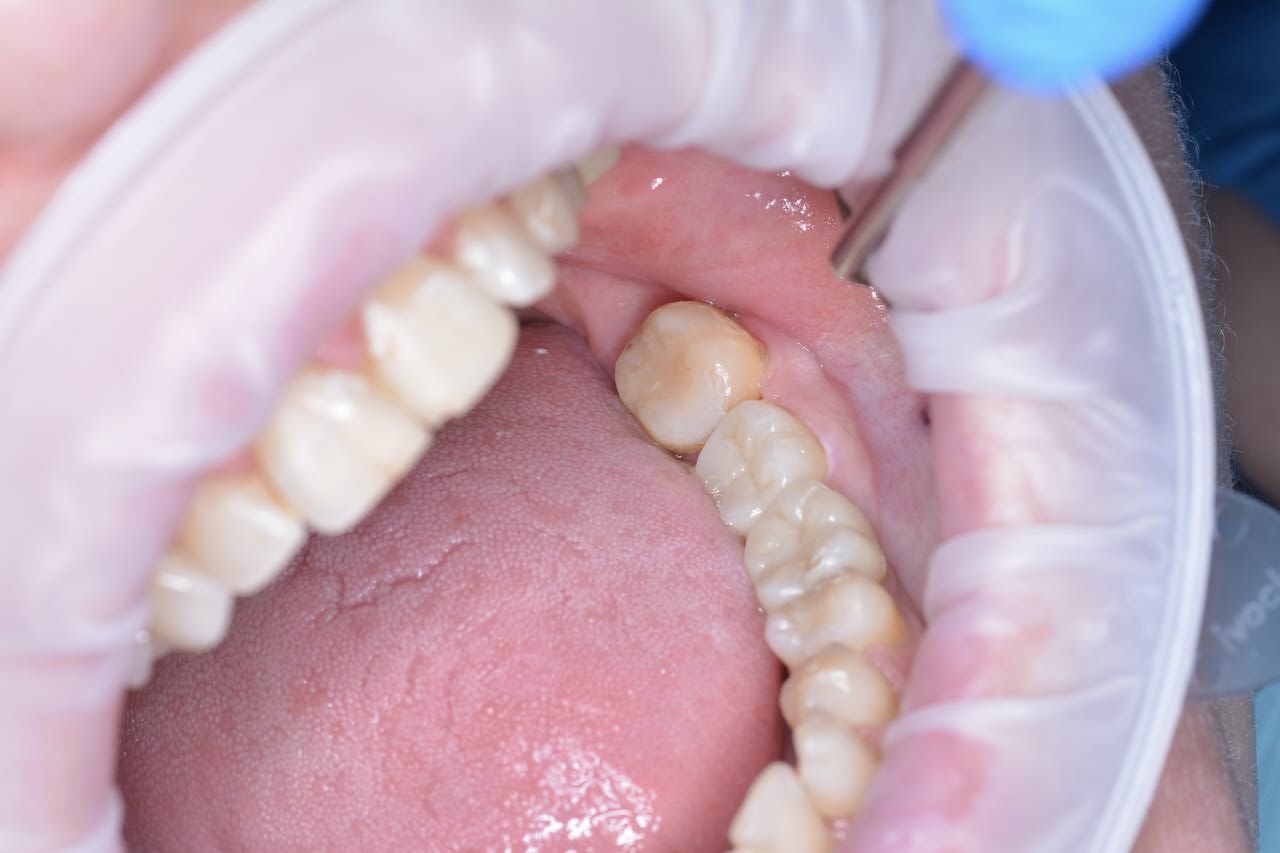

Замена старой металлокерамической коронки на циркониевую коронку на импланте в области 3.6. Протезирование зуба 3.7 циркониевой коронкой

Пациент обратился с жалобами на множественные сколы в области старой металлокерамической коронки на импланте 3.6 и для замены старой пломбы в области зуба 3.7. (ранее депульпированы)

Проведено перелечивание зуба 3.7. Из-за большого размера кариозной полости, истончение стенок зуба, для защиты и восстановления эстетики, принято решение установить коронку. Зуб 3.7 подготовлен для протезирования, сняты слепки.

В течение недели изготовлены и установлены циркониевые коронки на имплант 3.6 и зуб 3.7.